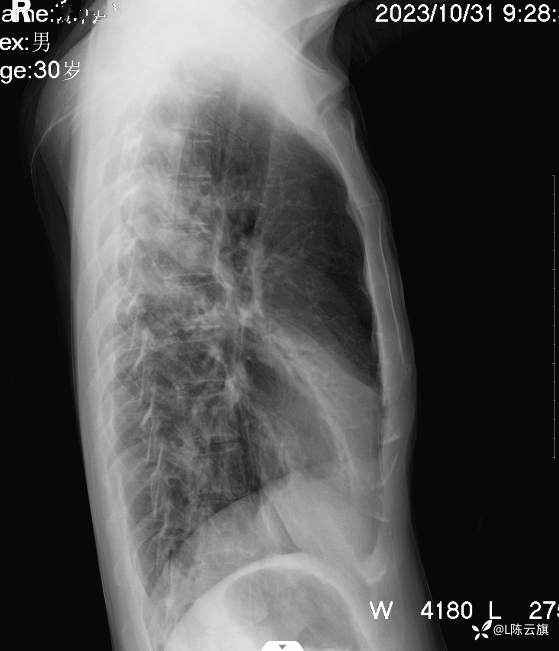

病例[每周胸片] 207 正侧位胸片 该如何诊断?(结果已公布)

患者男,30岁,精神病长期住院患者。咳嗽、咳痰二天伴发热、胸痛,体温38.5度。听诊两肺干湿啰音。